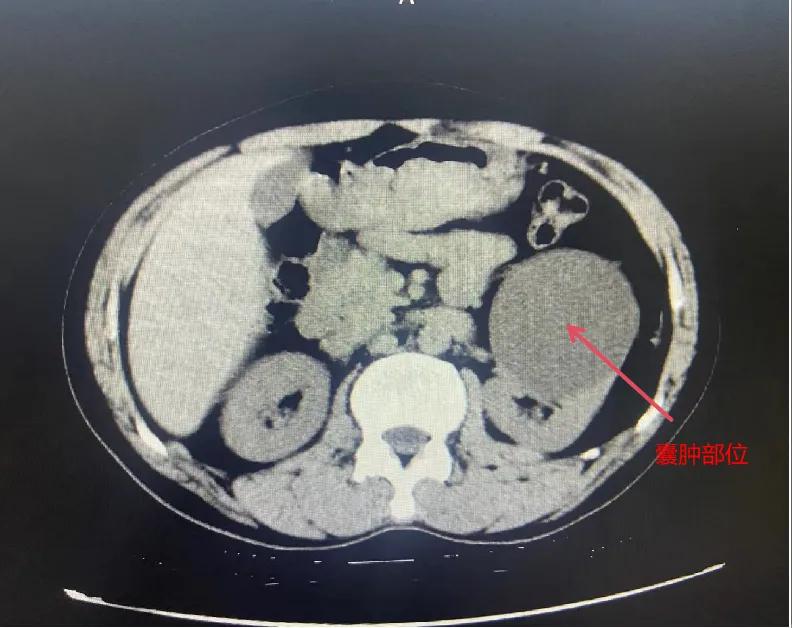

漯河市骨科醫院泌尿外科開展后腹腔鏡下腎囊腫去頂減壓術

近日,漯河市骨科醫院(漯河醫專二附院、漯河市立醫院)連續收治2例腎囊腫患者。泌尿外科主任閆衛甫和副主任醫師王金柱等醫師團隊經討論研究后,決定為患者采取后腹腔鏡下腎囊腫去頂減壓術,經過手術室、麻醉科等科室大力配合成功完成手術。

閆衛甫表示,后腹腔鏡技術是一種微創外科手術方法,它通過在后腹腔(即腹膜后的空間)建立一個手術空間,利用腹腔鏡器械進行手術操作。這種技術特別適用于泌尿系統等后腹腔臟器的手術。與傳統手術相比具有創傷小、恢復快、并發癥少、視野清晰等優點。與前腹腔鏡相比則具有對腹腔臟器干擾較少的優點。目前,后腹腔鏡手術主要用于腎囊腫去頂減壓術、腎上腺腫瘤切除、早期腎癌根治術、腎腫瘤剜除術等。

腎囊腫是一種常見的腎臟良性疾病,其發病率逐年增加。近年來隨著腹腔鏡技術的迅速發展,后腹腔鏡下腎囊腫去頂減壓術成為治療腎囊腫的主要方法。該手術具有創傷小,手術時間短,術中出血少,術后康復快,出院時間短等優點,并且術后復發率低,被認為是治療腎囊腫的理想術式。(盧 闖 聶方方 劉 旭 袁錦鈺)